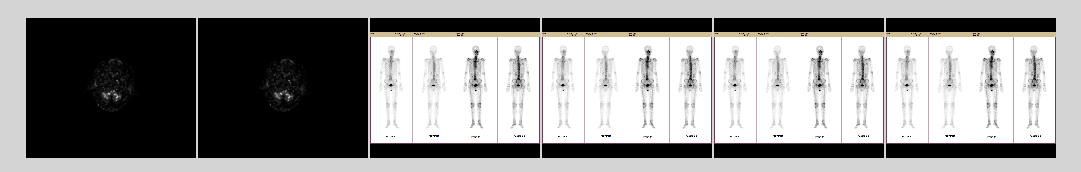

显示结果: